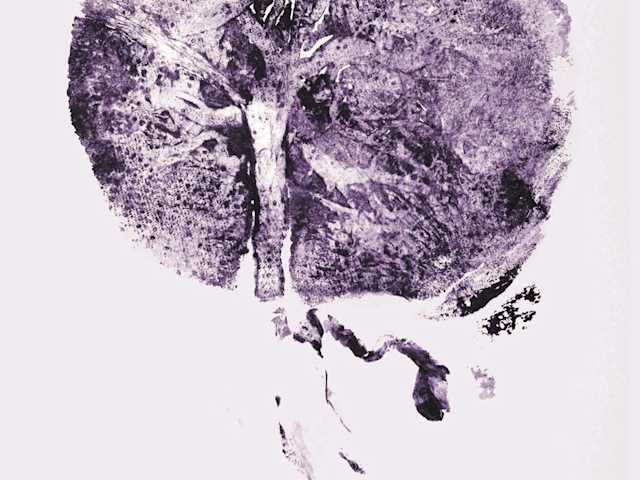

Die Embryonalentwicklung Des Menschen Springerlink